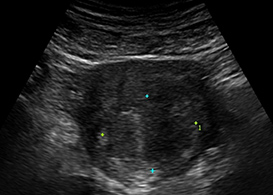

실시간 초음파 영상

The best treatment for humans안전한 치료를 위한 초음파 에너지 이동 경로 파악,

하이푸 시술의 핵심은 초음파 집속 에너지를 병변에 정확히 조사하는 것이며.

정밀판독 기술은 병변의 위치와 더불어 초음파 에너지의 이동경로를

파악할 수 있도록 합니다.

Artificial Intelligence - Software System사람의 몸은 끊임없이 움직입니다. 정확한 치료를 위해서는 실시간으로

움직이는 병변의 위치를 파악할 수 있어야만 합니다.

더욱 안전한 치료를 위한 이지스로앤산부인과의 경쟁력입니다.